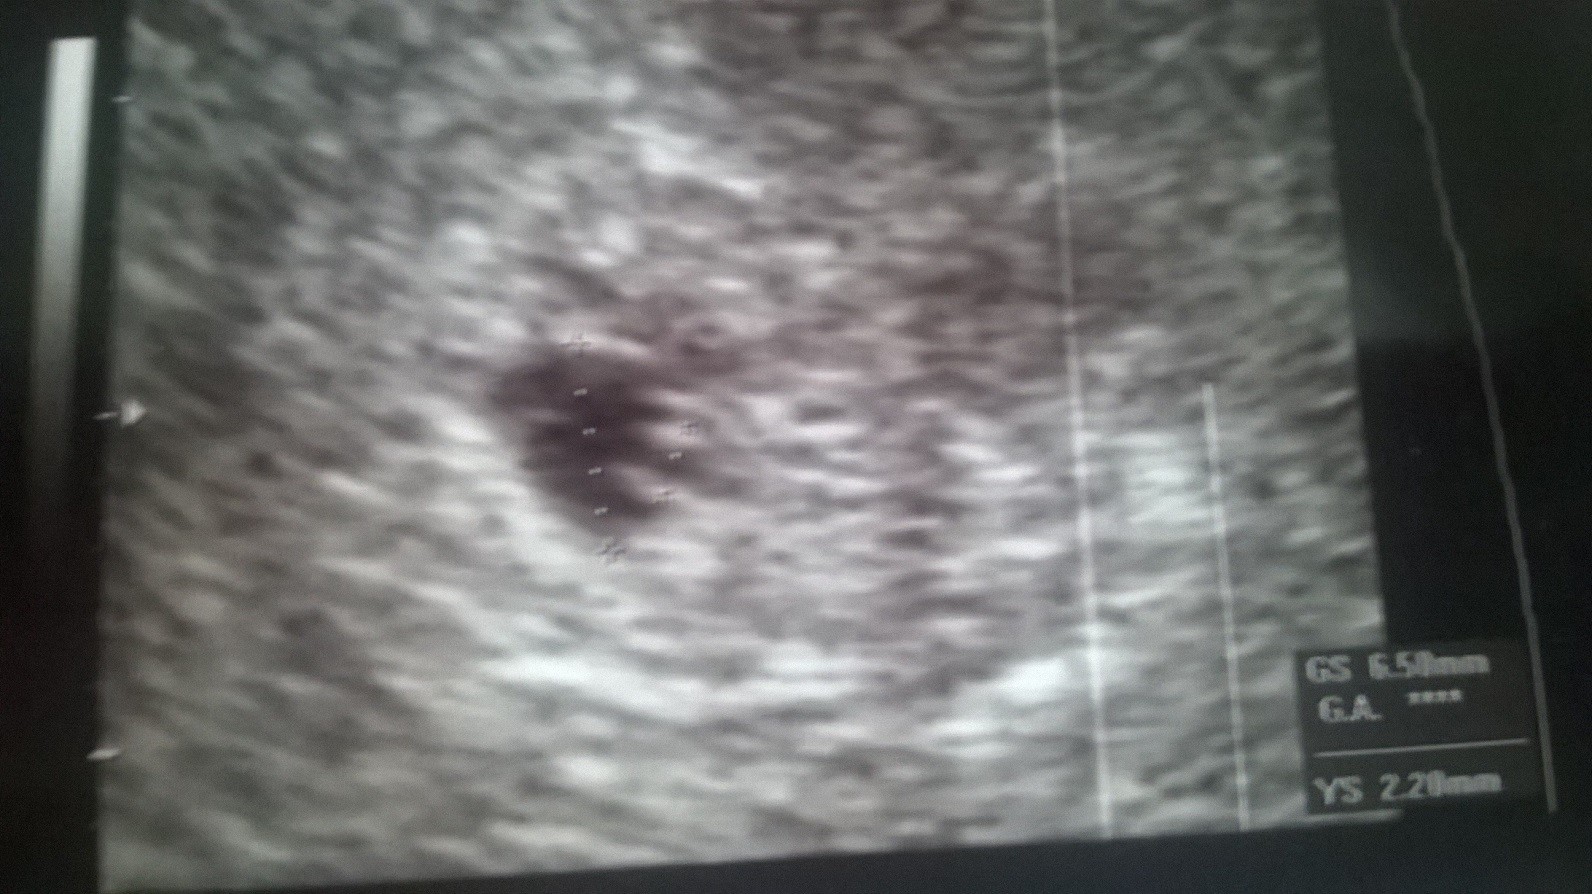

Patrząc na pomiary to faktycznie wydaje się, że coś jest nie tak, ale zobacz jak kiepski jest obraz na tych pierwszych dwóch. Tam milimetr w tą czy w drugą już robi różnicę. A co do wymiarów to nie brałabym pod uwagę tych robionych przez twoją byłą gin, bo po prostu się nie przykładała. Tak na prawdę po prostu trzeba czekać na rozwój sytuacji i wierzyć, że będzie dobrze.